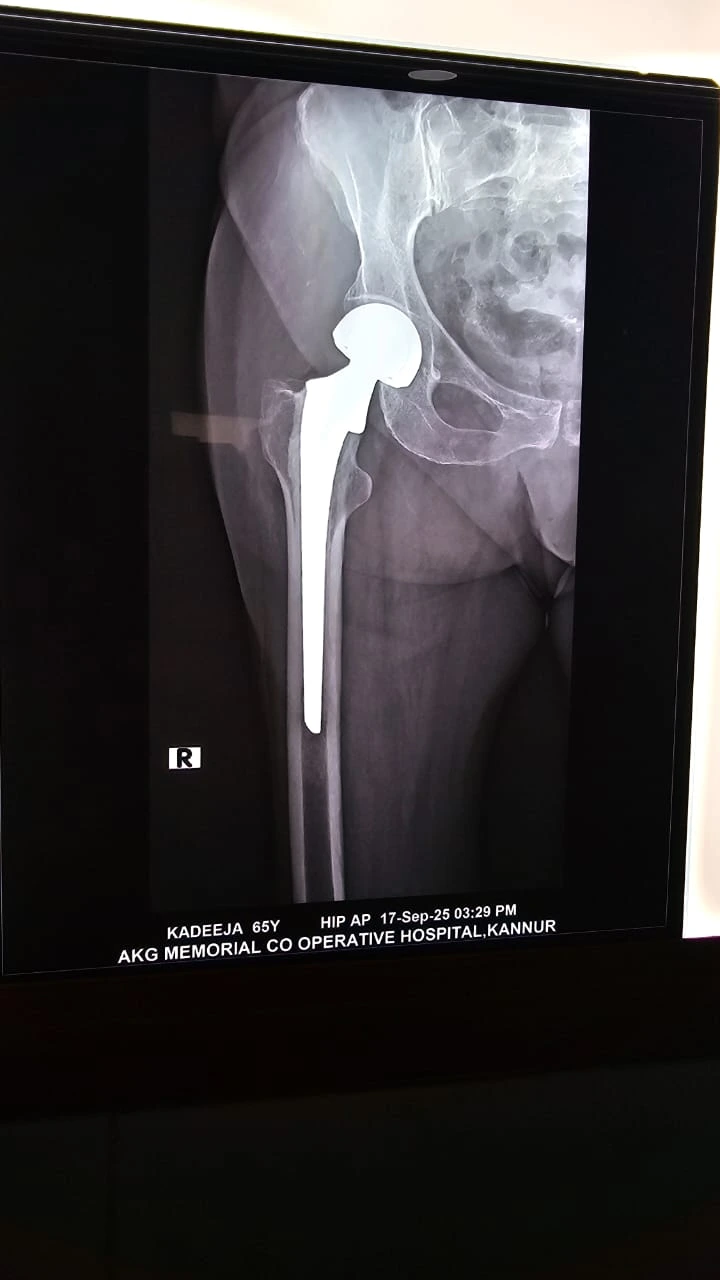

Image gallery